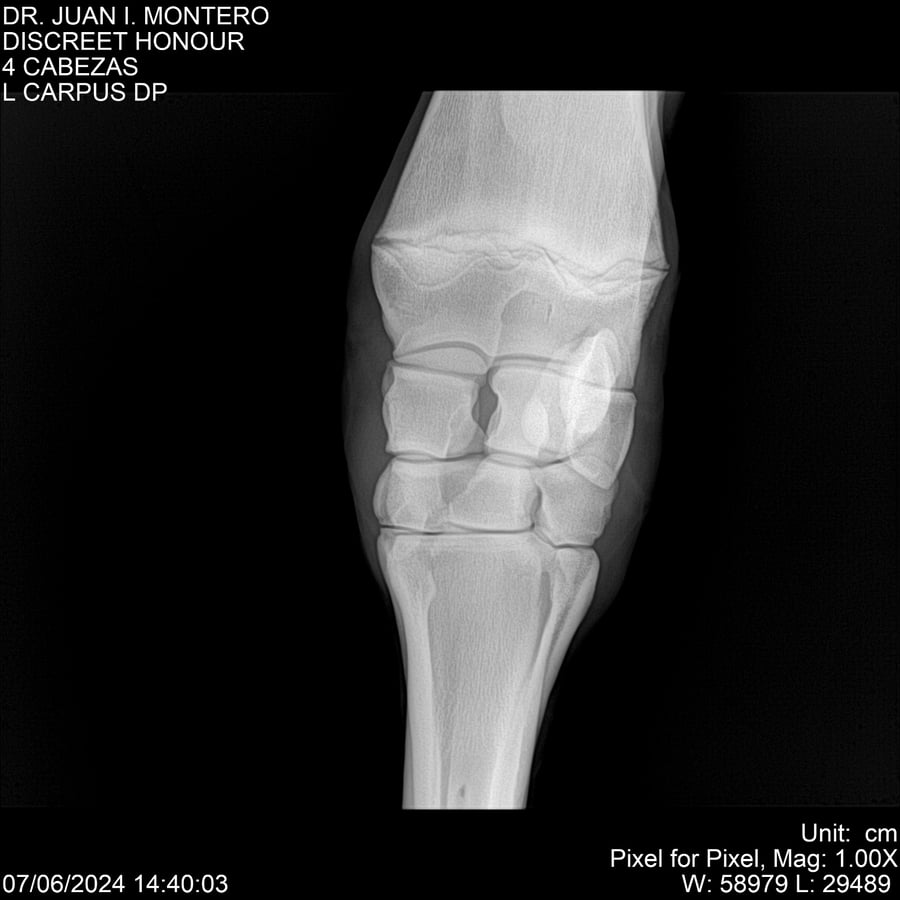

LOTE 6, DISCREET HONOUR 🔥 🔥 🔥 Lote Anterior Volver al remate Lote Siguiente Ficha Contacto Montevideo - Ficha del Lote Identificador: #281093 Categoría: Yeguarizos Montevideo - 82 Visualizaciones ClicData Contacto Empresa: Abelenda N. R., Walter Hugo Nombre*: Teléfono* : E-mail* : Mensaje Enviar Registrese gratis Este contenido Exclusivo está disponible sólo para usuarios registrados Ingresar